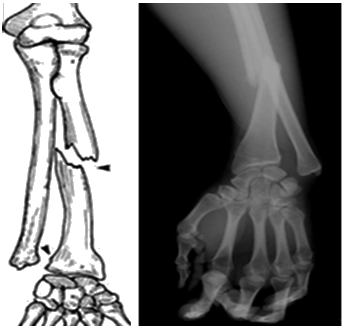

蓋氏(Galeazzi)骨折:橈骨干下1/3骨折合并尺骨小頭脫位